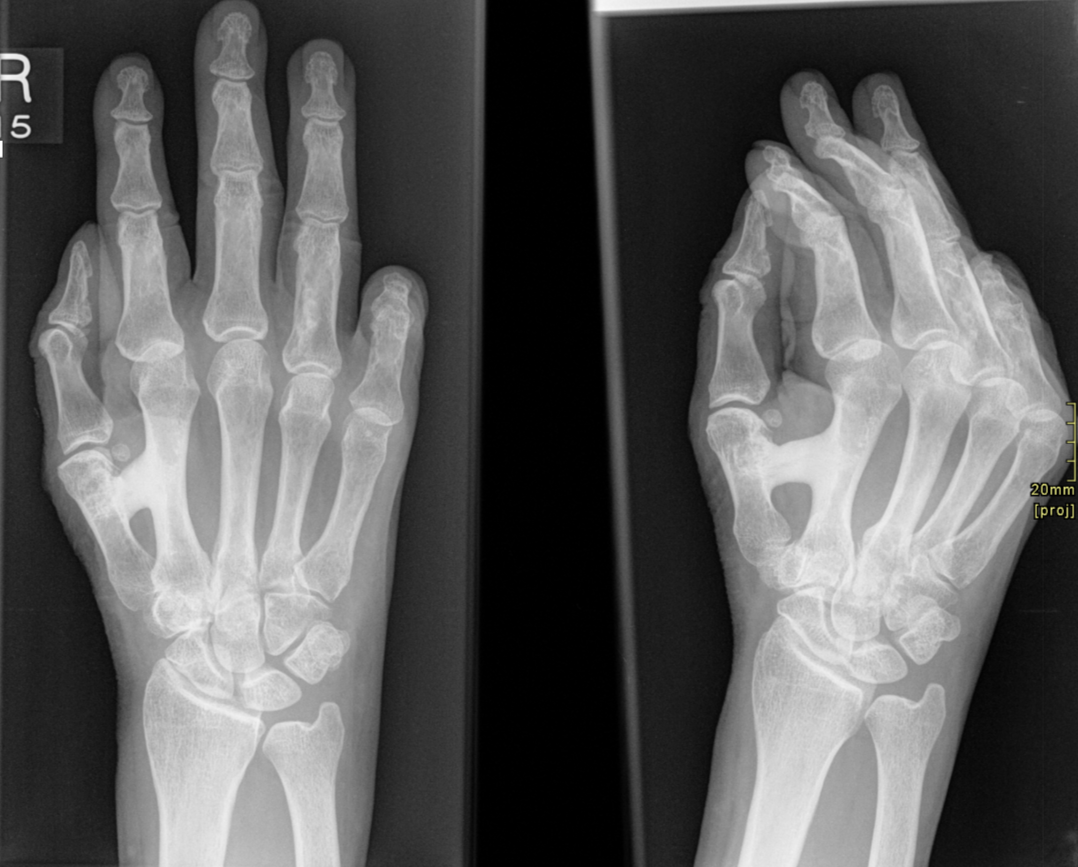

Ripon Hand - fused metacarpal dysplasia